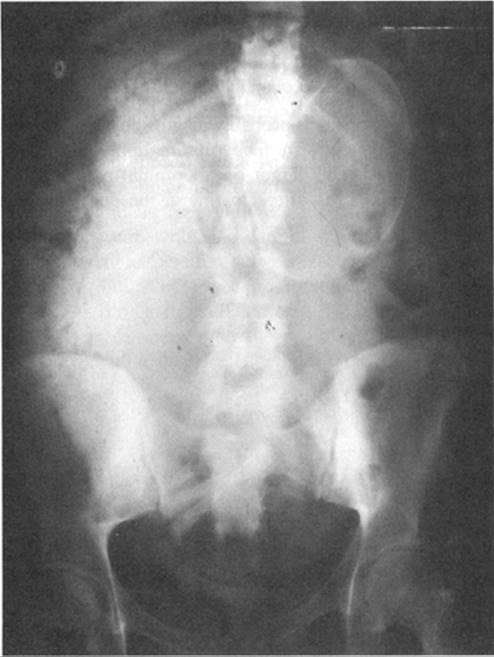

The diagnosis of cord prolapse should be suspected in any patient who develops fetal heart rate abnormalities after rupture of the membranes, either spontaneous or artificial. The heart rate abnormalities usually observed are sustained bradycardia and, less frequently, profound variable decelerations (Fig. 21.5). All such patients should be promptly examined or reexamined and the diagnosis confirmed by palpation of the cord alongside the presenting part or in the cervix or vagina.

FIG. 21.5. Fetal monitor tracing associated with umbilical cord prolapse.